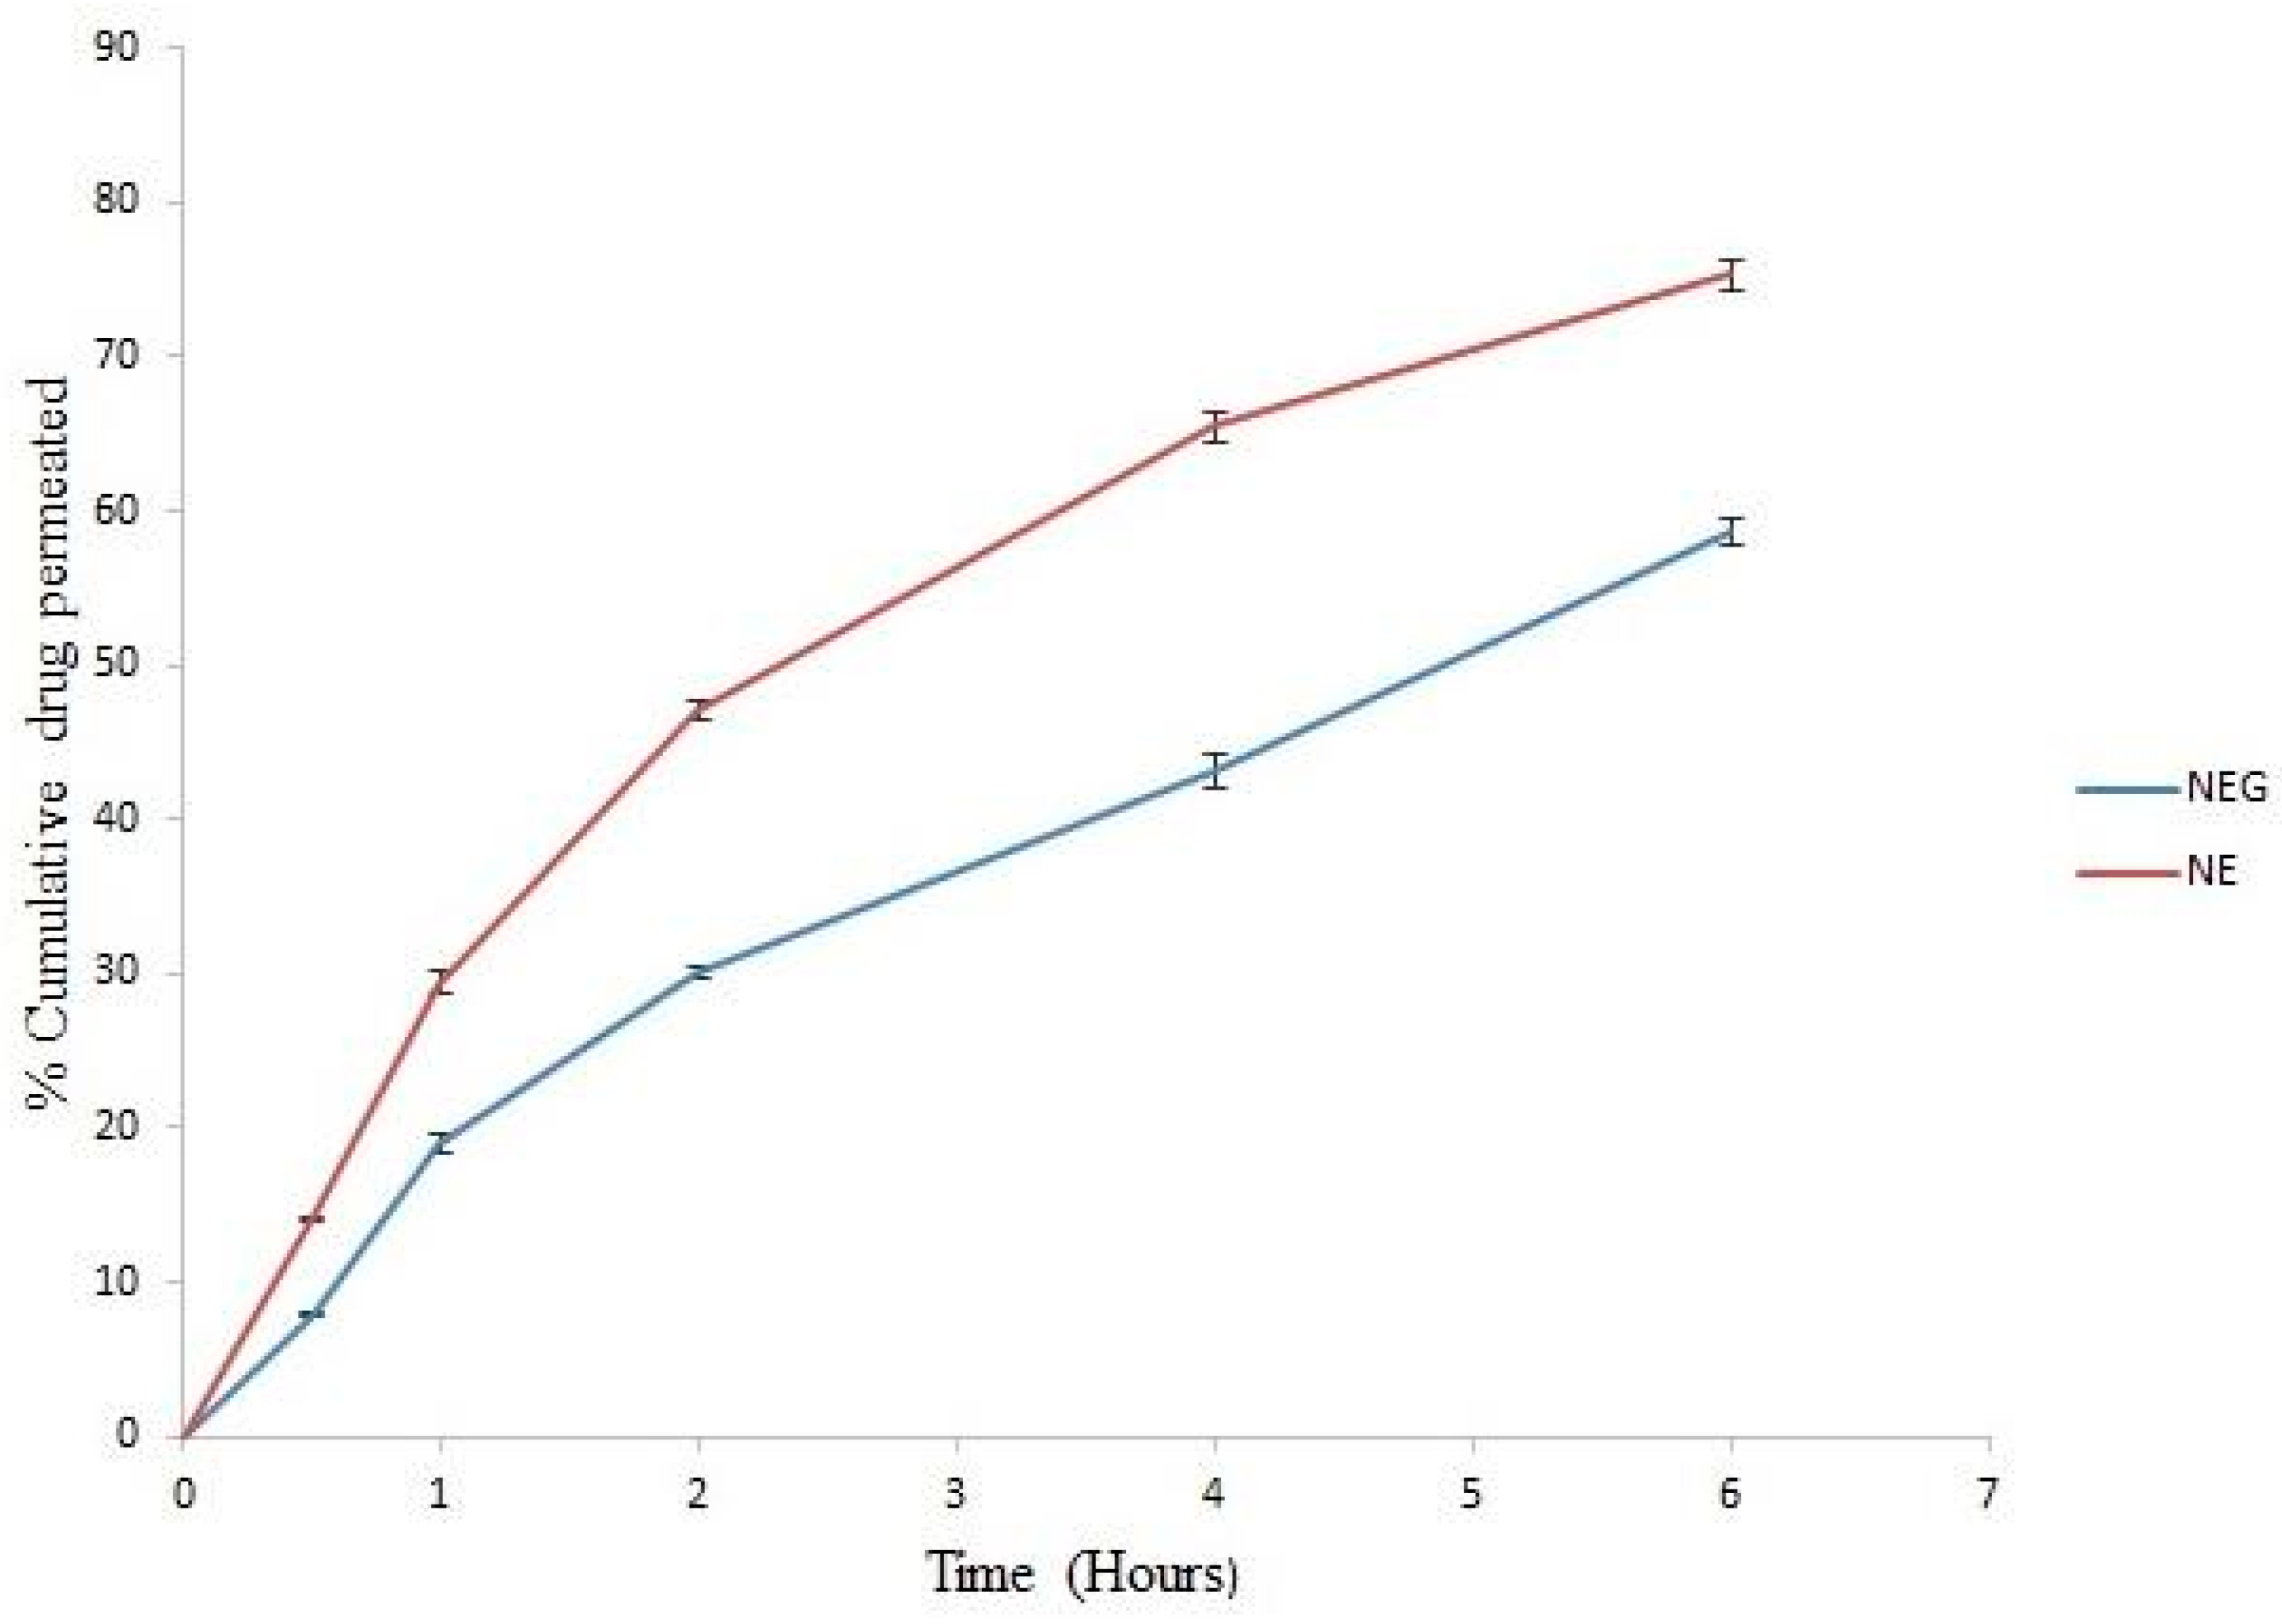

3.9. Ex Vivo Permeation Study